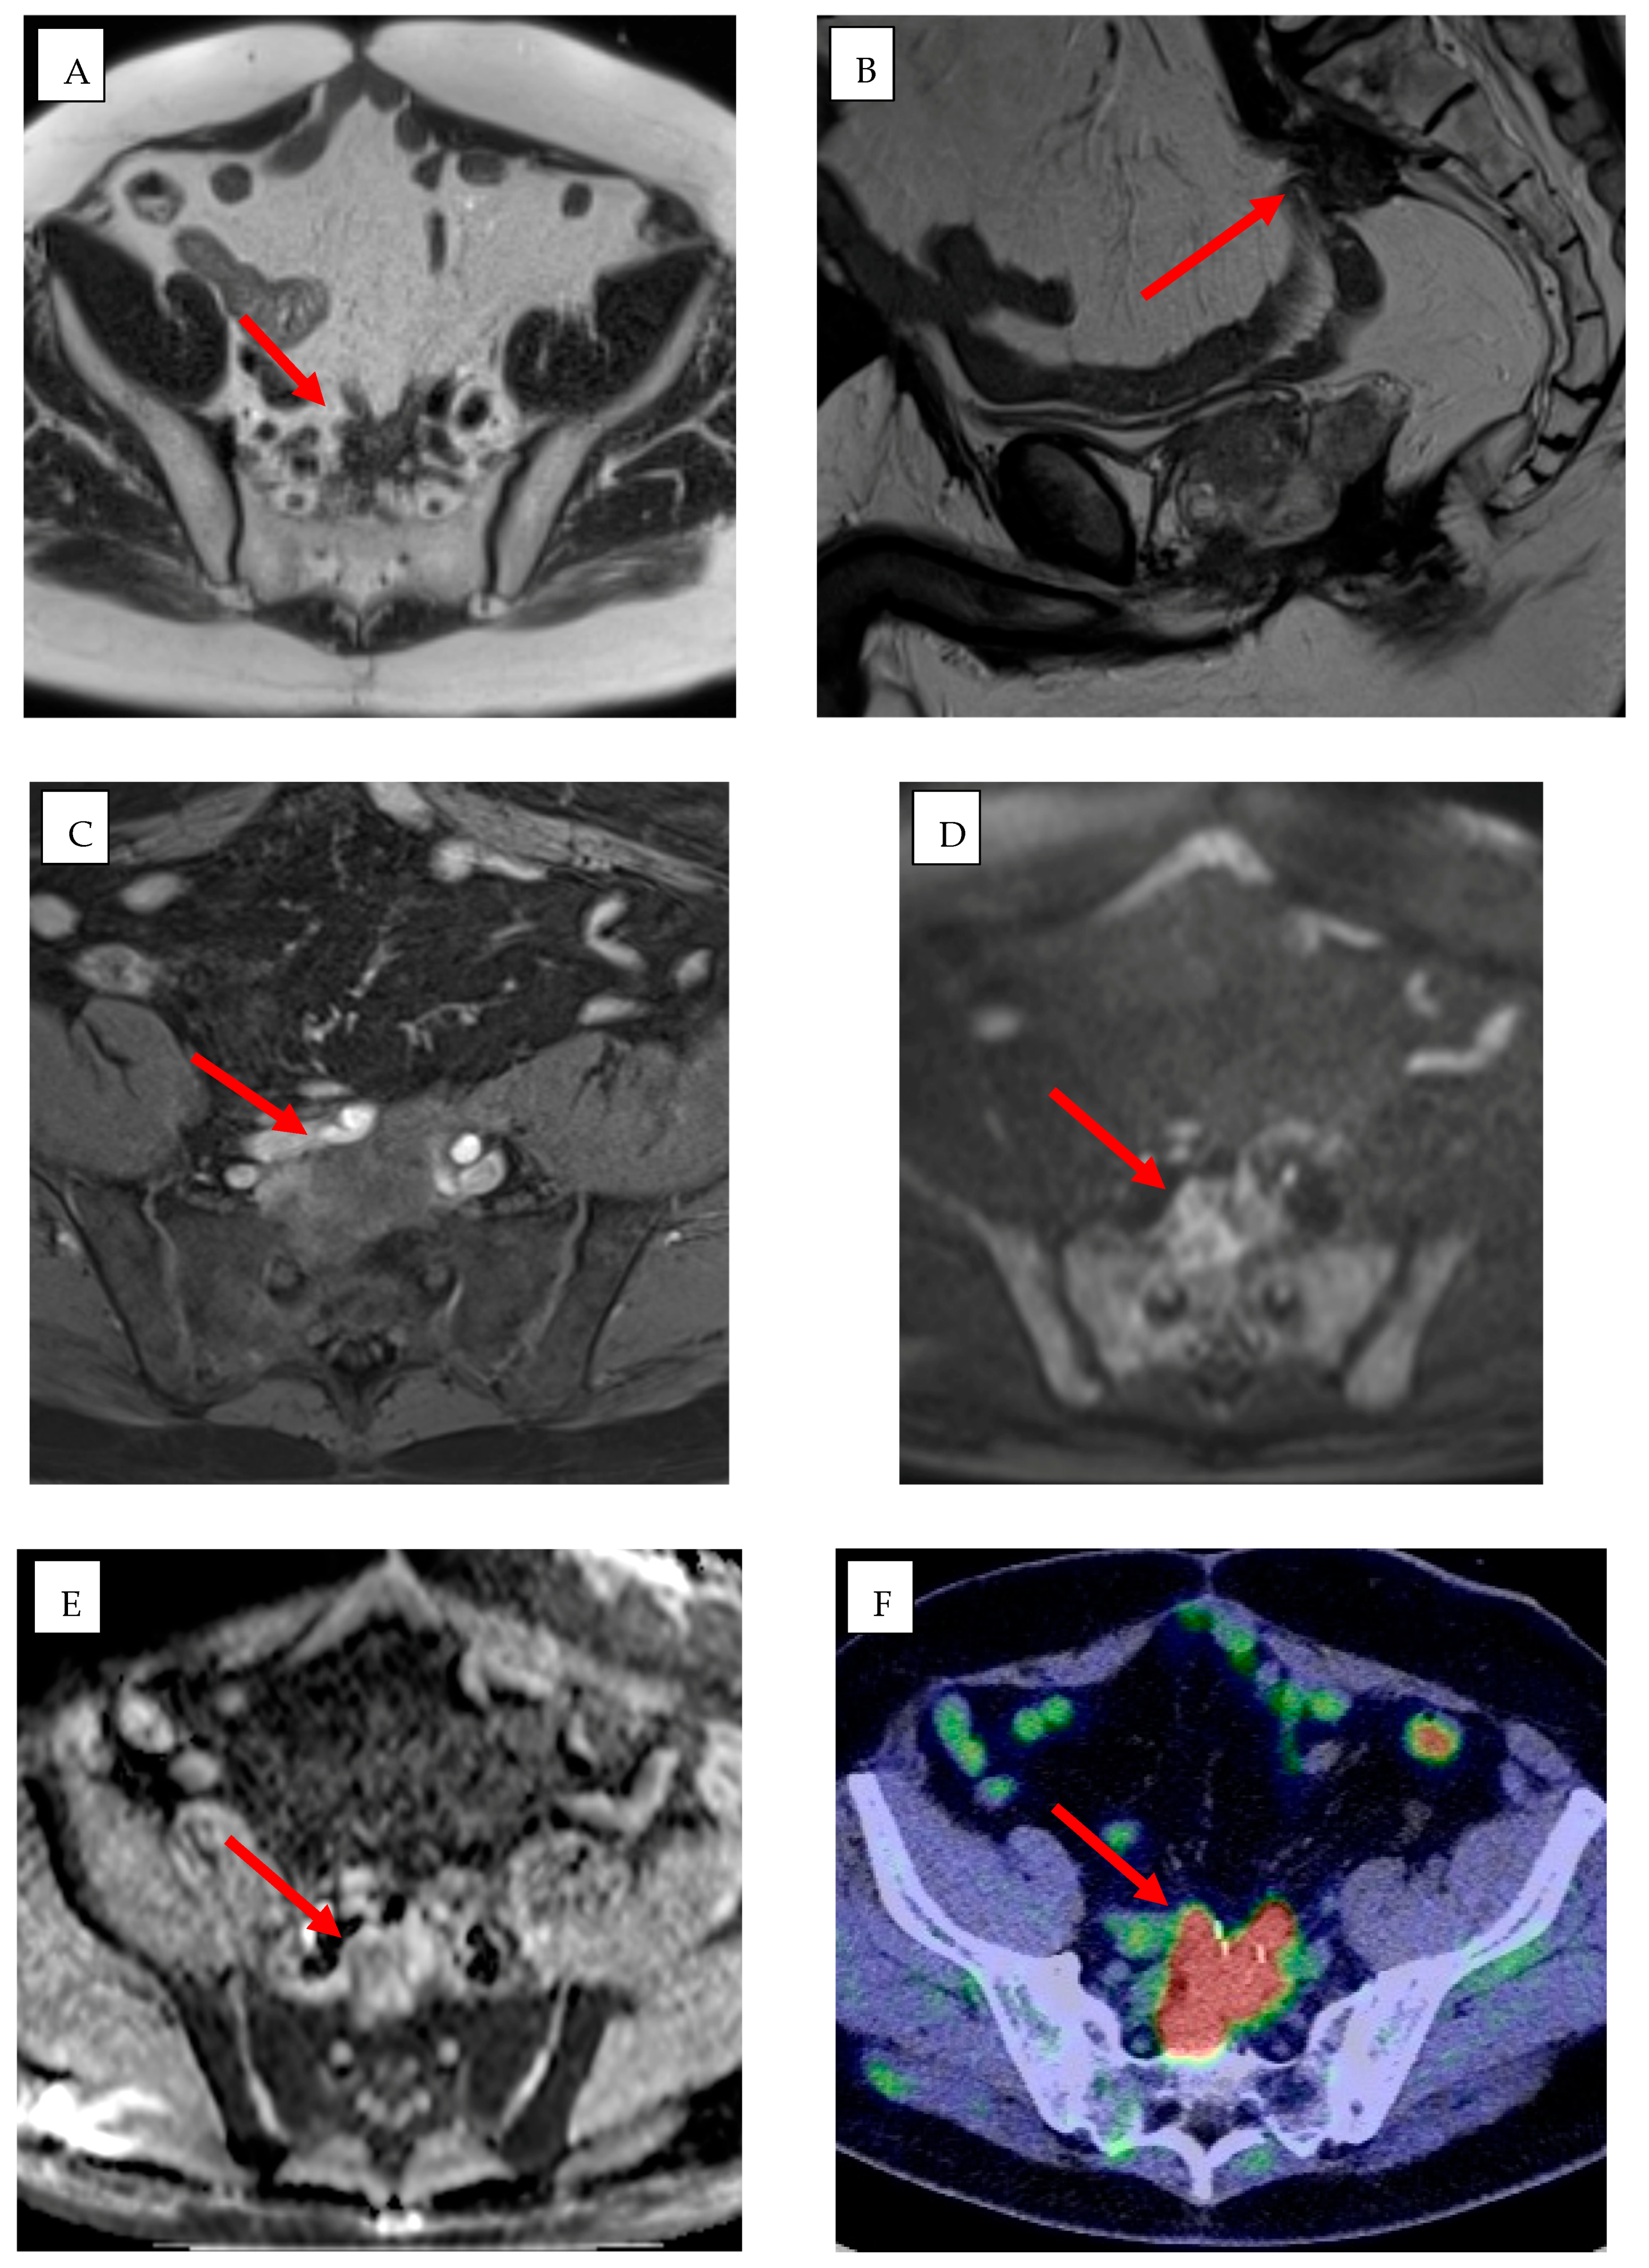

| Multimodal Fusion Imaging (CT/MR/PET + US/CBCT) | TACE, ablation, biopsies, vascular malformations | AI-supported registration and alignment of multimodal datasets; real-time anatomical matching | Improved lesion localization and targeting; reduced procedural time and radiation exposure | Accuracy depends on registration precision; requires training and expensive equipment |

| Fusion Imaging | Clinical fusion applications | Angle et al. [101] | Automatic/semiautomatic registration for multimodal fusion | CT | Ablation, liver tumor | Improves targeting and procedural accuracy. |

| Clinical fusion applications | Zhong et al. [100] | Automatic/semiautomatic registration for multimodal fusion | CT | Ablation, liver tumor | Improves targeting and procedural accuracy. | |

| Registration and alignment | European Society of Radiology [95] | Automatic/semiautomatic registration for multimodal fusion | CT, US, PET | Fusion-guided interventions | Improves lesion visualization and targeting. | |